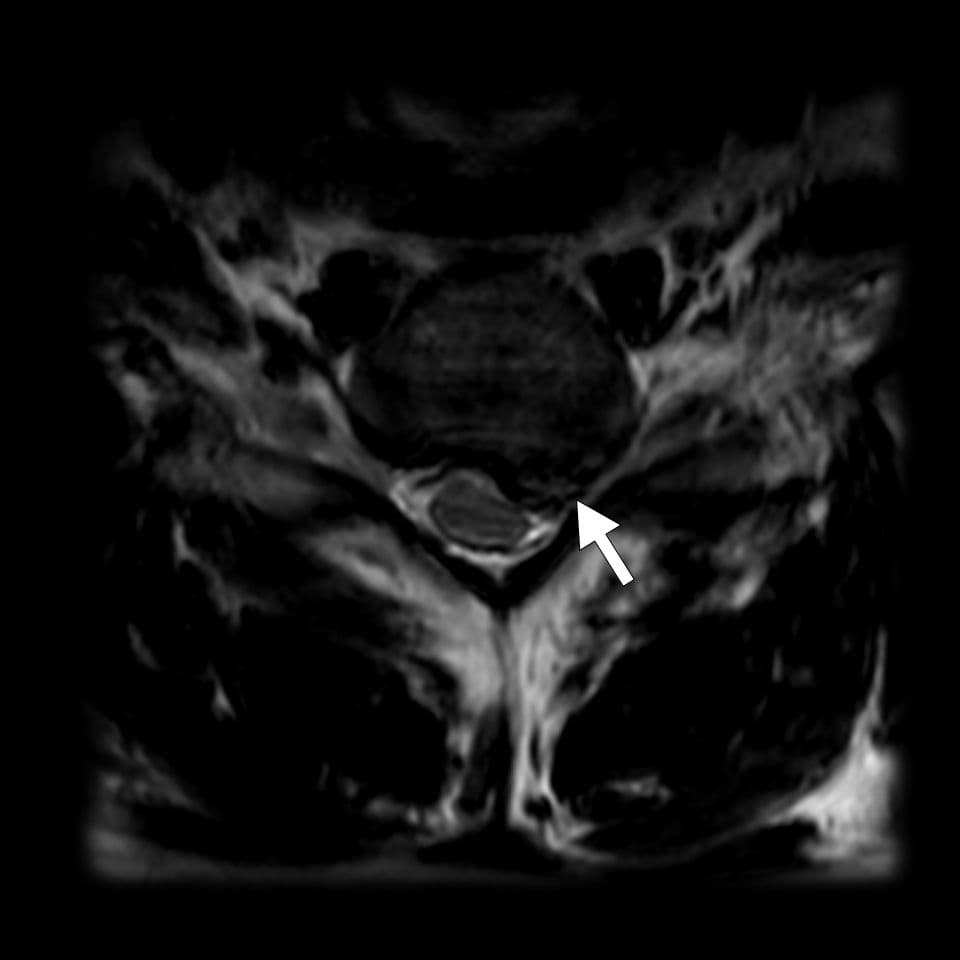

Conflit disco-radiculaire C7

Souffrance radiculaire de la racine de C7 par une hernie discale

MRI